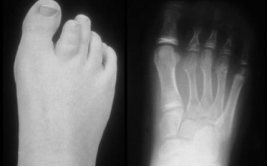

图2-5幼年型特发特发性关节炎

10岁,右足第二趾骨及跖骨较短,提示发育迟缓,是骨骼生长紊乱的表现